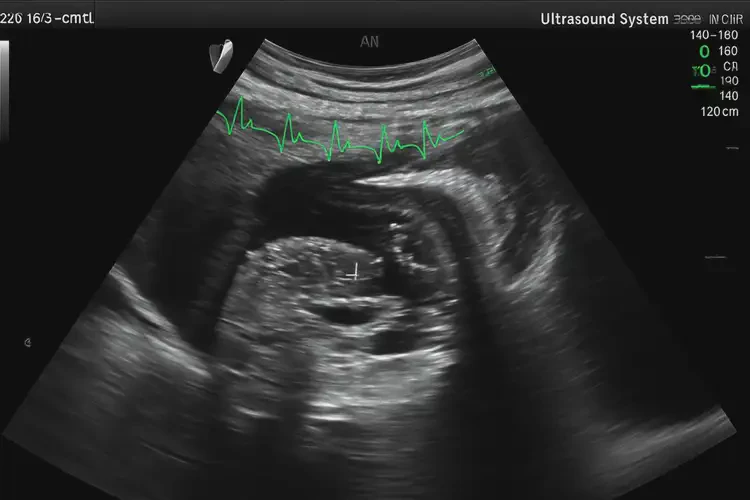

懷孕10多天胎心100多寶寶還能要嗎(圖2)